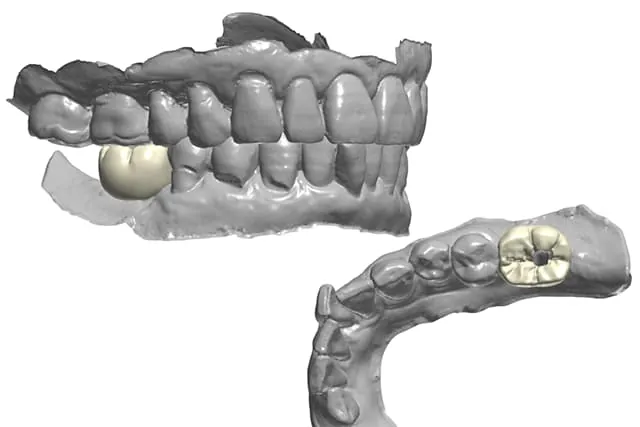

仮歯のデータからより噛みやすい被せ物を

当院のプレミアムプランでは、最終的な被せ物を着けるまで入れておく仮歯についても、プロビジョナルレストレーションと呼ばれる仮歯を使用します。

プロビジョナルレストレーションは、単に一時的なダミーの歯というものではなく、最終的に入れる被せ物と同じように精密に再現された仮歯です。プロビジョナルレストレーションを入れることで、歯や歯茎の形、噛み合わせや感覚的・審美的な違和感など、様々な点を実際の口腔内で微調整し確認していきます。

そうして仕上がったデータを基にすることで、最終的に完成度の高いより噛みやすいセラミック歯の被せ物を作成することができるのです。